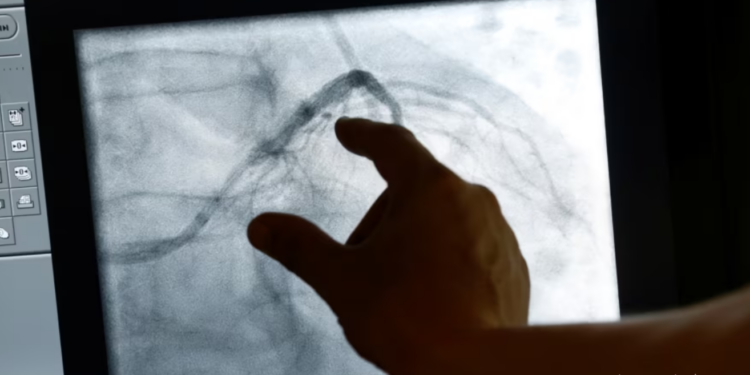

Studiuesit e inxhinierisë biomjekësore në Universitetin Johns Hopkins po punojnë për të transformuar kujdesin shëndetësor për pacientët me sëmundje të zemrës.

Ata tani mund të krijojnë një kopje dixhitale të zemrës së një pacienti dhe me ndihmën e inteligjencës artificiale mund të bëjnë parashikime më të sakta mbi rreziqet me të cilat përballen pacientët.

“Ne bëjmë imazhe me rezonancë magnetike të zemrës dhe më pas mund të kombinojmë të gjitha të dhënat klinike që njihen për pacientin. Kjo kombinohet me analizën e mbijetesës dhe ne mund të parashikojmë për një periudhë mbi 10 vjeçare nivelin e rrezikut të një pacienti nga një vdekje e papritur kardiake.”

Ndryshe nga imazhet e segmentuara që përdoren më shpesh sot, profesorja Natalia Trayanova thotë se imazhet e plota të zemrës,

ofrojnë parashikime më të sakta për pacientët që mund të kenë nevojë për defibrilatorë.

“Ne kemi algoritme që ofrojnë analiza më të hollësishme dhe një pasqyrë më të mire të gjendjes shëndetësore të pacientit”, thotë profesorja Trayanova.